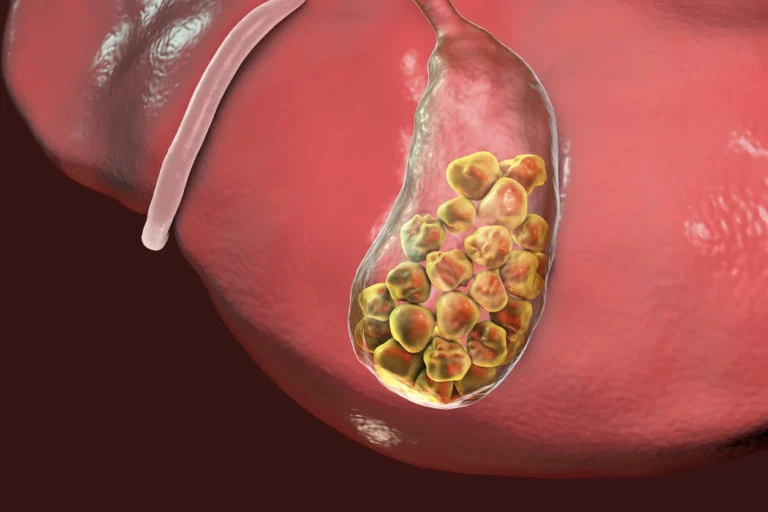

Kalau Terus Didiemin, Batu Empedu Bisa ‘Mengakar dan Mencakar’

Batu empedu nggak bakal hilang sendiri.

Dan kalau kamu biarin terus, risikonya makin nggak enak:

Nyeri bisa makin hebat sampai bikin kamu nggak bisa berdiri tegak

Bisa muncul demam, mual, muntah

Saluran empedu bisa ikut tersumbat → ini yang bikin kondisi makin kacau

Kenyamanan hidup kamu terganggu total

Semua ini nggak muncul tiba-tiba. Ada prosesnya.

Dan biasanya orang sadar… pas sudah sakit banget.